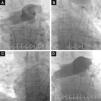

Dois dos nossos doentes foram‐nos referenciados por contraindicação para trombólise e o outro por trombólise ineficaz na melhoria do perfil hemodinâmico. No momento do procedimento, dois doentes encontravam‐se sedados e sob suporte ventilatório, e todos doentes tinham suporte aminérgico. Foi realizada punção da veia femoral comum direita e colocado um introdutor 7F. Com um cateter pig tail angulado 6F foi realizada arteriografia do tronco da AP e arteriografias seletivas das artérias pulmonares direita e esquerda. De seguida, um fio‐guia hidrofílico 0,035’ foi posicionado na AP afetada e foi avançado o cateter de duplo lúmen AngioJet® 6F. A ativação do cateter foi proximal a distal, tendo sido realizada uma a duas passagens completas. O procedimento foi repetido para as artérias lobares afetadas e para AP contralateral, se necessário. No final da intervenção procedeu‐se à revisão angiográfica (Figura 4). O procedimento deve ser interrompido assim que se verifique recuperação hemodinâmica ou se atinja o tempo de ativação total recomendado pelo fabricante, independentemente do resultado angiográfico final. Optou‐se pela implantação de pacemaker transvenoso temporário por via femoral no início do procedimento na última doente. Os doentes foram admitidos na UCIP no pós‐procedimento.

Imagens de fluroscopia durante arteriografia inicial do tronco pulmonar (mas mais seletiva para a direita), revelando TEP massiva bilateral com trombos nas artérias pulmonares principais e envolvendo todas as artérias lobares, com obstrução significativa do fluxo (A), cateter AngioJet® 6F posicionado na artéria pulmonar esquerda (B) cateter posicionado na artéria pulmonar direita (C) imagem final, revelando uma melhoria angiográfica discreta, contudo, acompanhada de melhoria imediata do perfil hemodinâmico e das trocas gasosas (D).